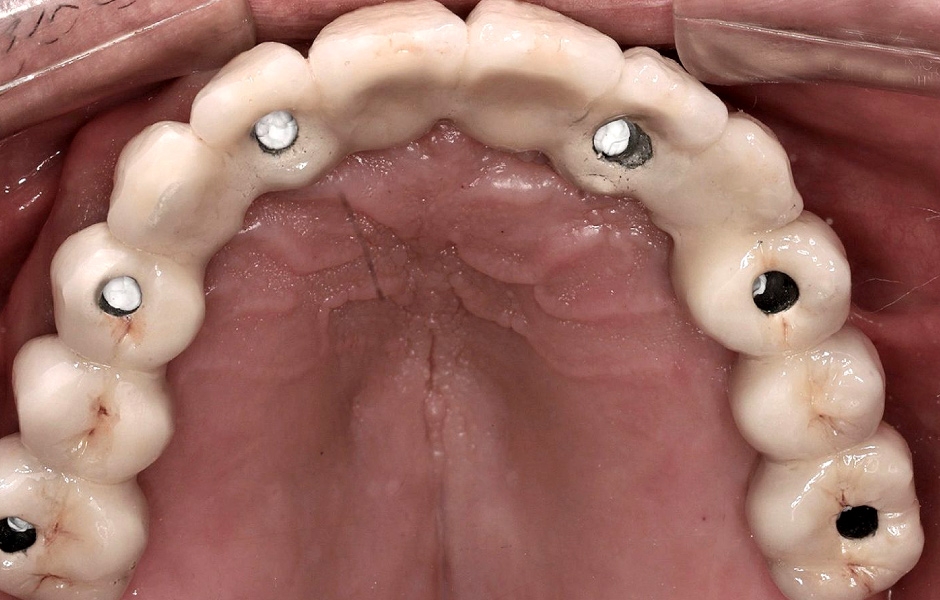

Definitivní náhrada byla nasazena a ověřena z hlediska estetiky, okluze a funkce (obr. 51–55). Panoramatický kontrolní snímek potvrdil, že všechny parametry protetického ošetření odpovídají očekávaným hodnotám (obr. 56).

Obr. 51

Obr. 52

Obr. 53

Obr. 54

Obr. 55